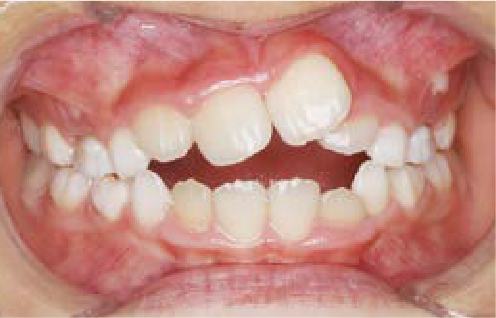

現役歯科医師の愛娘さんの治療

Nさん (矯正開始時:8歳)

Before

After

上あごの成長が少なく、特に前歯のガタガタが目立っていました。口呼吸のクセや飲み込み方に良くないクセが確認されました。

治療を終えて

マイオブレイスとBB1装置で上あごの成長を助け、鼻呼吸や正しい飲み込み方を身につけることで、きれいな歯並びとしっかり噛めるお口に変わっていきました。

姿勢やお口の機能を正しく整えたので、後戻りしない綺麗な歯並びを維持できています。もちろん非抜歯です。

主訴・治療内容 当院と交流のある歯科医師の先生が、ご自身のお子さまの治療を任せてくださいました。

「難しい歯並びでも永久歯を抜かず、全身の健康と顔立ちも考えて治療してくれる」と信頼していただいて治療開始。

治療期間 3年

費用 462,000円(税込)